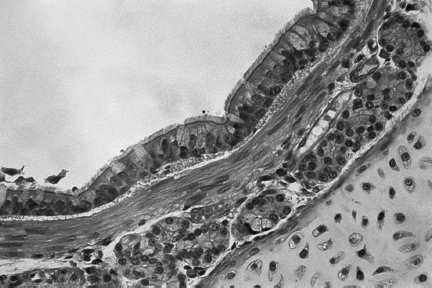

The image shown is a photomicrograph of a transverse section of part of the gas exchange system.

What describes the image?

1 )

a thin inner layer of ciliated epithelial cells on top of a layer containing cartilage, supported by elastic fibres

2 )

a very thin epithelial lining with walls containing elastic fibres, surrounded by many blood vessels

3 )

an inner layer of ciliated epithelial and goblet cells on top of elastic fibres, supported by an outer layer consisting of cartilage

4 )

an inner layer of ciliated epithelial and goblet cells on top of loose tissue with mucous glands, supported by a continuous ring of cartilage